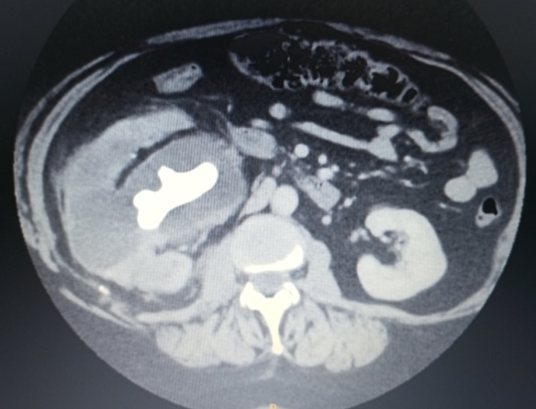

The patient was admitted to the Urology department for further investigation and treatment, where she developed worsening pain and fever of 38-39ºC. An abdominopelvic CT scan with intravenous contrast (Figure. 2) revealed a large staghorn calculus in the RK with significant

pelvicalyceal dilation. No contrast elimination was observed. Inflammatory changes in the perirenal fat were noted. A portocaval adenopathy conglomerate was present. Several hypoenhancing hepatic lesions were identified.

Figure 2: Abdominopelvic CT scan with intravenous contrast staghorn calculus in the RK, significant pelvicalyceal dilation. Inflammatory changes in the perirenal fat (green arrows). A portocaval adenopathy conglomerate (red arrow). Hypoenhancing hepatic lesions (yellow arrows).